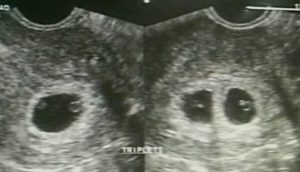

A recent news report by GMA Saksi revealed the ultrasound of the presidential daughter. In the ultrasound, it conveyed a triplets.

Confirmed in the previous report, the presidential daughter and her family is expecting a triplets in the next months. As of the present, Mayor Inday Sara is bearing them on their seventh month.